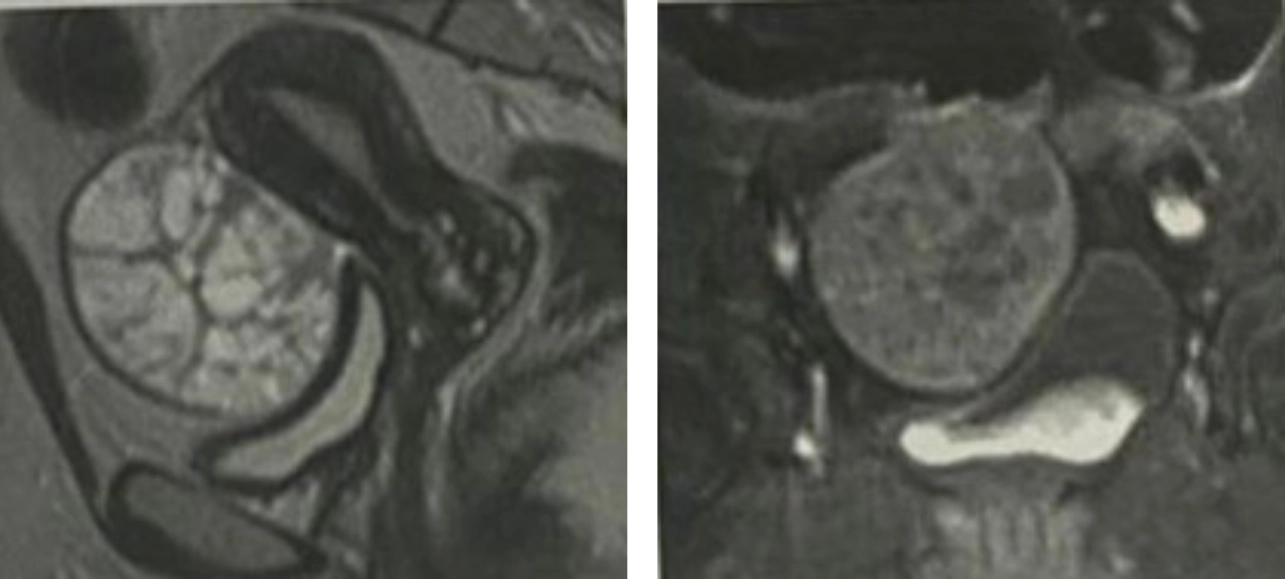

2. MRI

The patient was referred to do a complementary MRI with contrast to confirm the diagnosis and assess the extent of the mass and lymph node involvement.

MRI confirmed the Swiss cheese appearance of the multi-locular ovarian mass and the enhancing septae in the post contrast sequences.